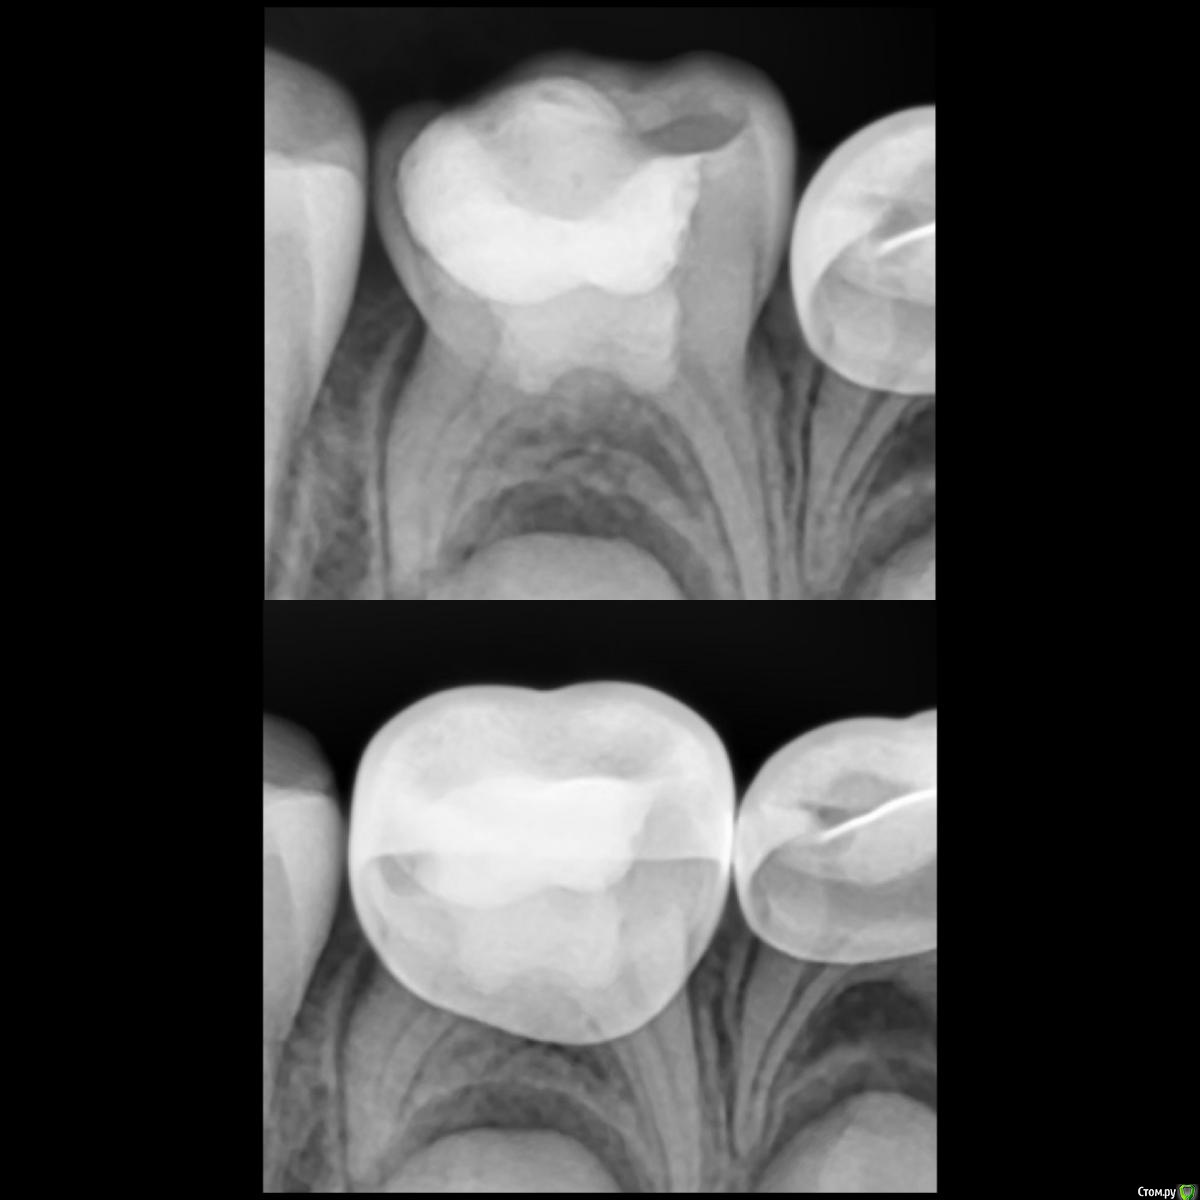

CRAZYDUCK Опубликовано 22 мая, 2018 Автор Поделиться Опубликовано 22 мая, 2018 Сначала текст , ниже фото .Даша , 5,5 лет . Лечение кариеса 5.5, кариеса 5.3 , необратимый пульпит 5.4. Продолжительность 1час 30 минут ( с момента входа в кабинет, выбора мультика и до расставания).«Скрытый» кариес медиальной контактной поверхности 5.5 подтверждён RVG. Я указала на него синими стрелочками ( листайте). 5.3 обработала рондофлекс и немного микромотором .5.4 - видно , что после ампутации гемостаза нет( полость заполнена кровью). Экстирпация машинный sx, ручные файлы 25.02; промываю гипохлорит 3%. В каналах Йодотин.культя 5.4 восстановлена IRM. Коронку фиксирую на айрекс-цем.Контрольный снимок. 1 Ссылка на комментарий

CRAZYDUCK Опубликовано 22 мая, 2018 Автор Поделиться Опубликовано 22 мая, 2018 Фото. 2 Ссылка на комментарий